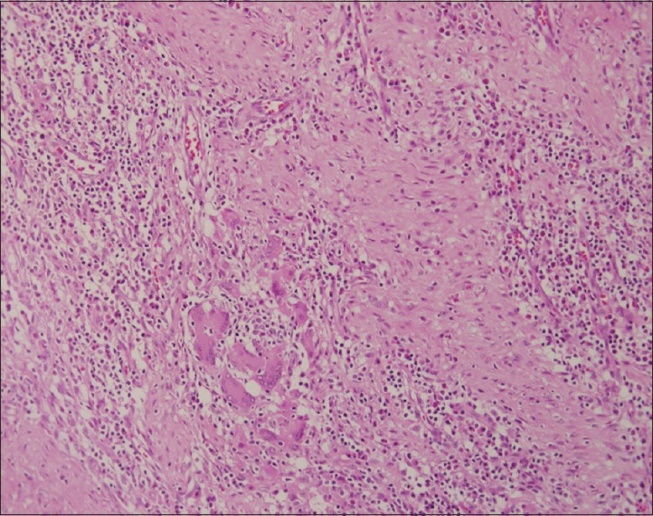

A 27-year-old female presented with a history of upper abdominal pain, nausea and off and on vomiting of 12weeks duration. The pain had an intensity of 7/10 and was a burning type of pain with no reference or radiation. She stated that for the previous 2weeks her pain was aggravated by food intake. She denied any alarming symptoms in the form of loss of appetite and weight loss. There was no history of hematemesis or melena. She had no history of NSAID intake or tuberculosis contact. Her past medical records showed an appendicectomy eight years back. Her clinical examination was normal apart from mild epigastric tenderness and on evaluation, her hemoglobin levels were 14g/dl. She had a normal leukocyte count, and liver function and renal function were normal. Serum lipase and amylase levels were not elevated. An ultrasound of her abdomen did not indicate the presence of gallstones and all other organs were normal. She underwent upper gastrointestinal (GI) endoscopy to rule out a gastric ulcer due to the pain being aggravated by food. An upper gastroscopic examination revealed normal esophagus. There was 4 cm × 3cm bulge in the antral portion of her stomach, and the overlying mucosa was erythematosus (Figure 1). The fundus and body of the stomach were normal. There was no evidence of duodenal ulcer or growth. Rapid urease test for Helicobacter pylori was negative.A biopsy from the antral portion revealed chronic gastritis, but there was no evidence of Helicobacter pylori. The differential diagnosis of gastrointestinal tumor (GIST) was considered and resection of the nodule and biopsy was performed after color Doppler imaging ruled out the presence of vascular structures along the needle track. However, the microscopic examination (Figure 2) showed islands of pancreatic acini and ducts in the muscularispropria of the stomach. Several dilated ducts were seen extending through all the layers of the muscularispropria. There was evidence of fibrotic reaction and scant mixed inflammatory infiltrate was observed in the area. There was no evidence of malignancy.

Figure 2 histopathology of the resected nodule showing islands of pancreatic acini.